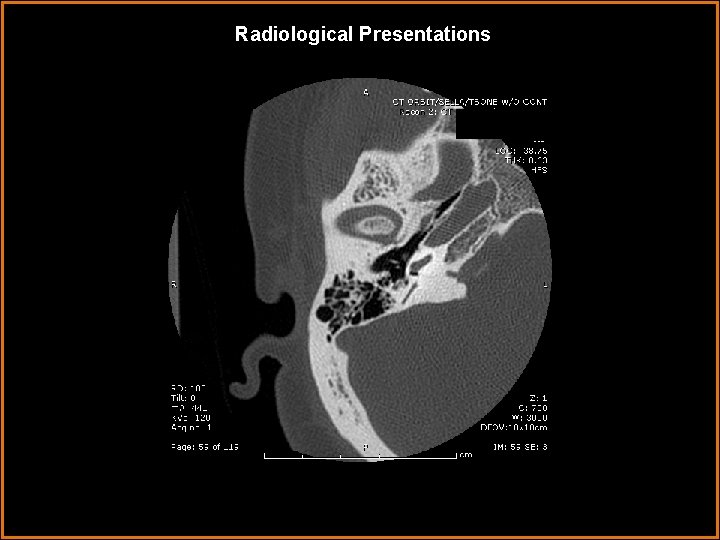

Findings and Differentials Findings: Soft tissue 5 mm nodule arising from the cochlear promontory in the middle ear. Clearly separated from facial nerve (its horizontal segment can be seen on the first several axial slices running anteromedial to posterolat, just under the lateral semicircular canal). Scutum intact, epitympanic recess clear. Differentials: • A. Glomus tympanicum • B. Cholesteatoma • C. Facial nerve schwannoma • D. Persistent stapedial artery

Discussion • Glomus Tympanicum typically presents as pulsatile tinnitis in a middle age female (vascular lesions=pulsatile). It arises from glomus bodies along the tympanic branch of CN IX, called Jacobson’s nerve. On MRI it is an enhancing vascular lesion. It classically arises from the cochlear promontory (arrows below). When large, it tends to engulfs bone but does not erode it. Coronal Axial